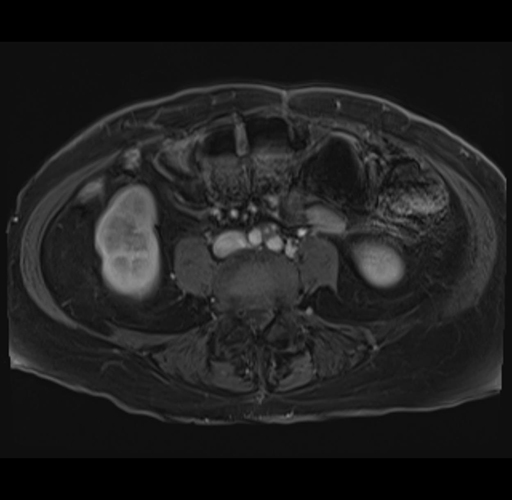

MRI T1